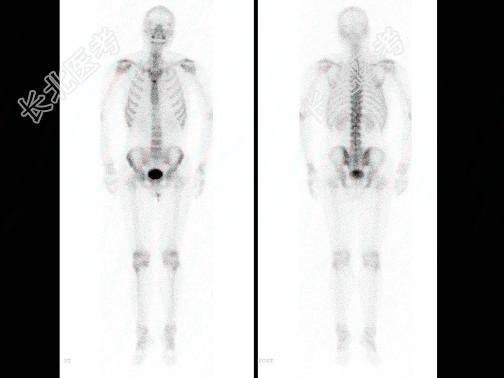

多项选择题男,34岁, 肝癌术后,诉胸背痛3个月, 行Tcm-MDP全身骨显像如图,对此描述正确的是 ( )

A、胸12椎体“冷区”

B、胸12无明显异常

C、胸12椎体骨转移瘤可能性较大

D、胸12椎体为溶骨性破坏

E、消化道肿瘤骨显像“冷区”常见